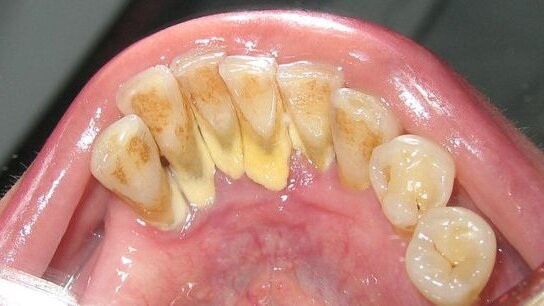

Po niedokładnym szczotkowaniu na zębach pozostaje miękki, białożółty nalot, który przekształca się w płytkę nazębną. Ta stopniowo ulega mineralizacji, twardnieje i zamienia się w trudny do usunięcia kamień. Widać go przy krawędzi dziąseł, to tzw. kamień naddziąsłowy. Wraz z nim pojawiają się bakterie, bo płytka i kamień to dla nich doskonała pożywka. Powstawaniu osadu sprzyja dieta bogata w cukry i skrobię. „Znaczenie mają też czynniki genetyczne, źle założone plomby czy chropowata powierzchnia szkliwa” – wyjaśnia dentystka.

Kamień nazębny ukrywa się też głęboko w kieszeniach zębowych. Sprzyja mu utrzymujący się długotrwały stan zapalny dziąseł, ponieważ na skutek ich rozpulchnienia płytka nazębna łatwiej wnika w rejon szyjki zębowej. Tam mineralizuje się i już jako twardy kamień ze zdwojoną siłą odpycha dziąsła od zębów. Kamień rozwijający się poddziąsłowo ma kolor ciemnobrązowy lub czarny. Rozprzestrzeniając się, niszczy system utrzymujący zęby w zębodołach. Tak dochodzi do wszelkiego rodzaju paradontopatii. Choć sama paradontoza uważana jest za chorobę autoimmunologiczną i nie do końca znane są jej przyczyny, to wszelkiego rodzaju paradontopatiom można zapobiegać. Wystarczy profilaktycznie 2 razy w roku czyścić zęby w gabinecie, a w przypadku skłonności do odkładania się kamienia, nawet częściej. „Także w przypadku już powstałych stanów zapalnych kuracja z zastosowaniem nowoczesnych urządzeń to sposób na uniknięcie interwencji chirurgicznej” – przekonuje dr Gnach-Olejniczak.